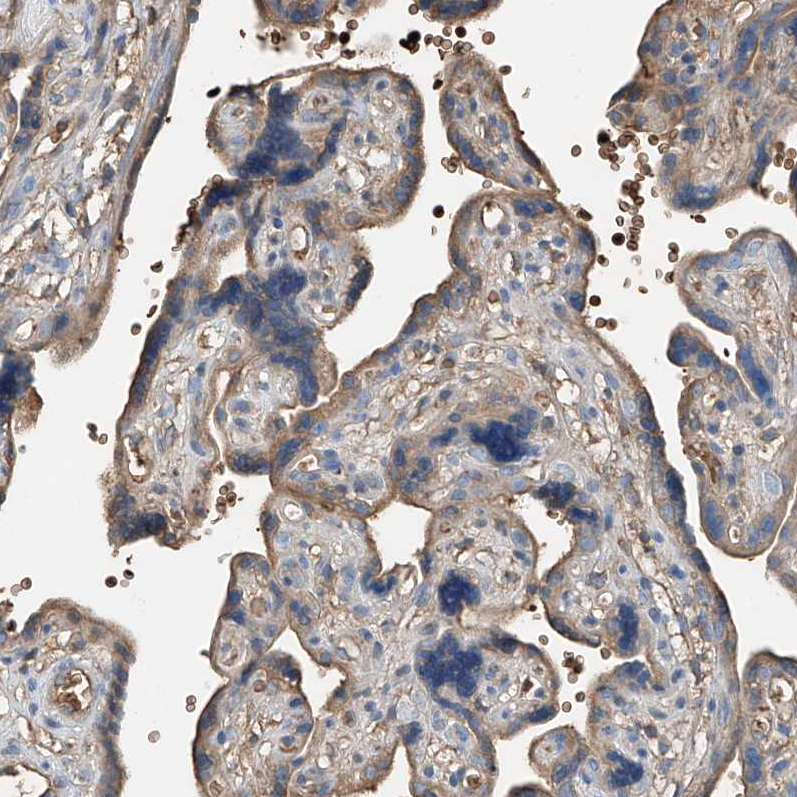

Immunohistochemical staining of human placenta shows moderate cytoplasmic positivity in trophoblastic cells.